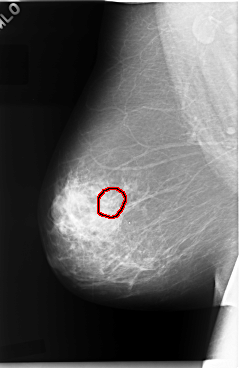

C_0045_1.RIGHT_MLO

FILE: C_0045_1.RIGHT_MLO.OVERLAY

TOTAL_ABNORMALITIES 1

ABNORMALITY 1

LESION_TYPE CALCIFICATION TYPE PLEOMORPHIC DISTRIBUTION CLUSTERED

ASSESSMENT 5

SUBTLETY 4

PATHOLOGY MALIGNANT

TOTAL_OUTLINES 1

BOUNDARY